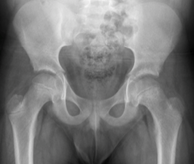

SCFE AI

SCFE Detection AI

Expert level detection of slipped capital femoral epiphysis using AI. 99% accurate.

A. Campion, A. Ha, B. Do, et al.